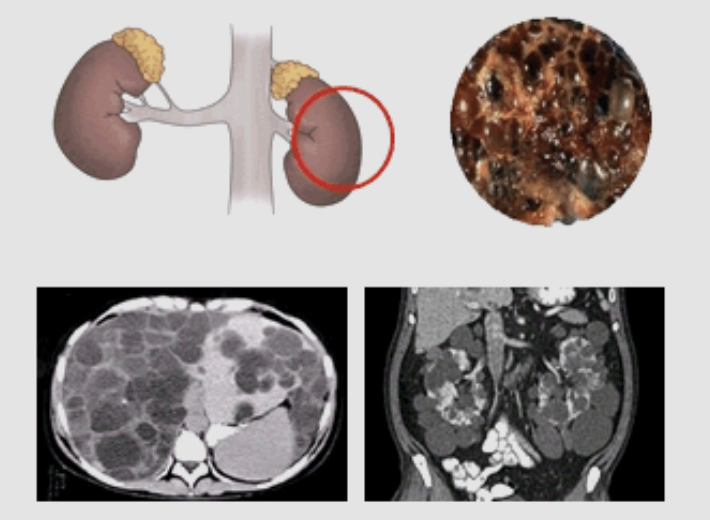

신장 석회화란?

신장 석회화는 신장 내에서 칼슘과 인이 과도하게 침착되는 현상을 말합니다. 이러한 상태는 신장의 정상적인 기능을 방해하고 신장 손상을 초래할 수 있습니다. 신장 석회화는 주로 고혈압, 당뇨병 같은 만성질환 또는 특정 약물 복용 등으로 발생할 수 있습니다.

신장 석회화 진단 및 검사 방법은?

신장 석회화를 진단하는 방법은 여러 가지가 있습니다. 혈액 검사는 신장 기능을 평가하고 혈중 칼슘 및 인 수치를 확인하는데 사용됩니다. 또한 요액 검사, 초음파, CT, MRI 등의 영상 진단도 신장 내 석회화를 확인하는 데 도움이 됩니다.